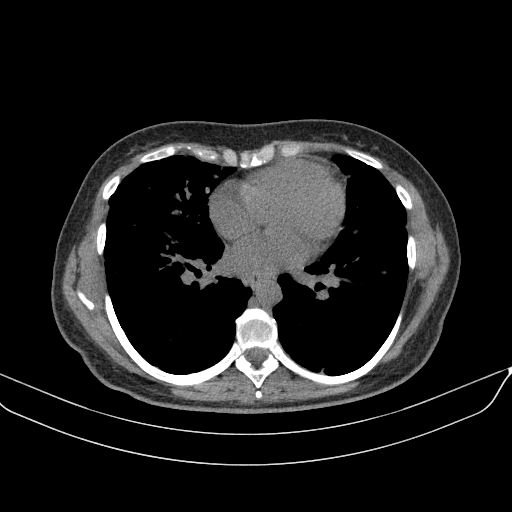

Image Grid

4Γ—3 grid: Rows show different image types (Original NATIVE, Reconstructed NATIVE, Original VENOUS, Generated VENOUS), Columns show windowing techniques (No Window, Lung Window, Mediastinum Window)

Original NATIVE CT scan (input)

Full window (WL 1023.5, WW 4095 β†’ Low βˆ’1024, High +3071)

Original VENOUS CT scan